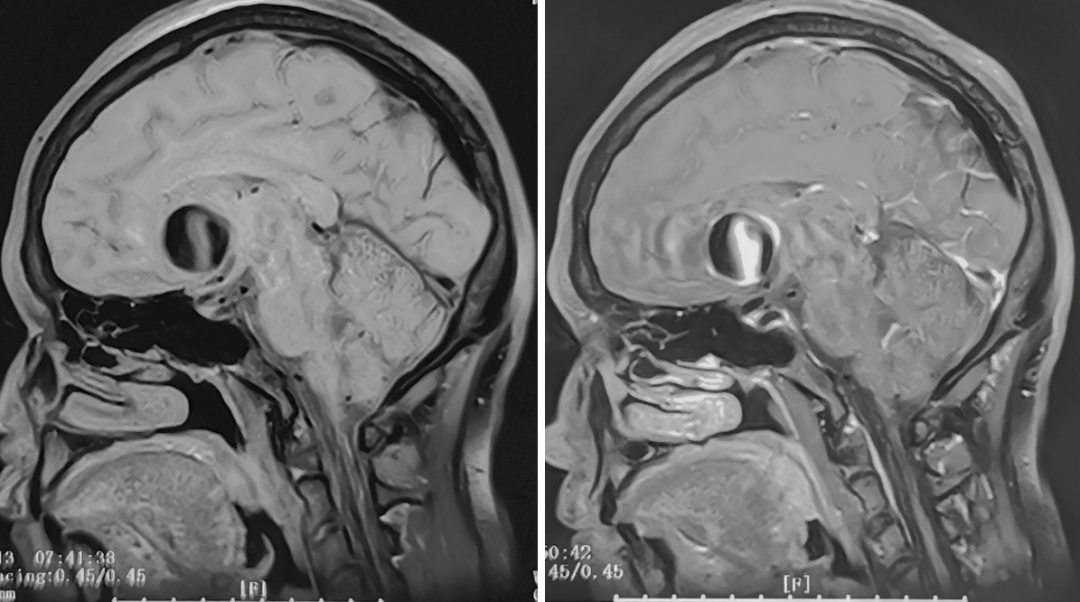

性别:女性,年龄:33 y.o

影像学阳性

术前诊断: